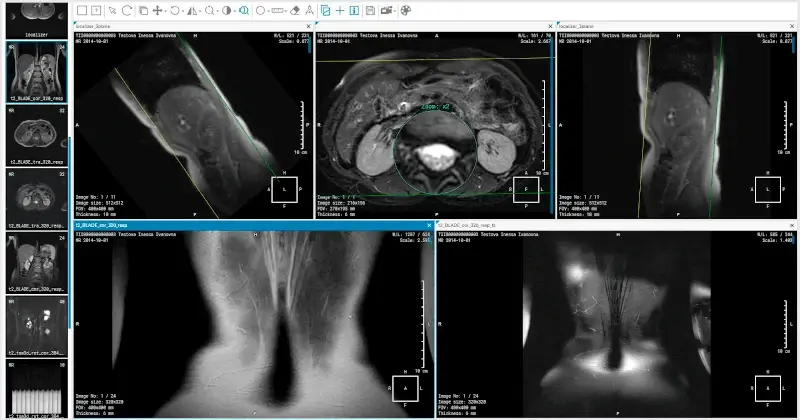

13. Ginkgo CADx

Ginkgo CADx is an advanced open-source application tailored for medical imaging provides a range of tools for visualization, analysis, and interpretation of various medical images.

Whether it’s DICOM, X-rays, CT scans, or MRIs, this software ensures seamless viewing and management. Beyond mere visualization, Ginkgo CADx supports a variety of image enhancement and annotation tools, aiding professionals in accurate diagnostics.